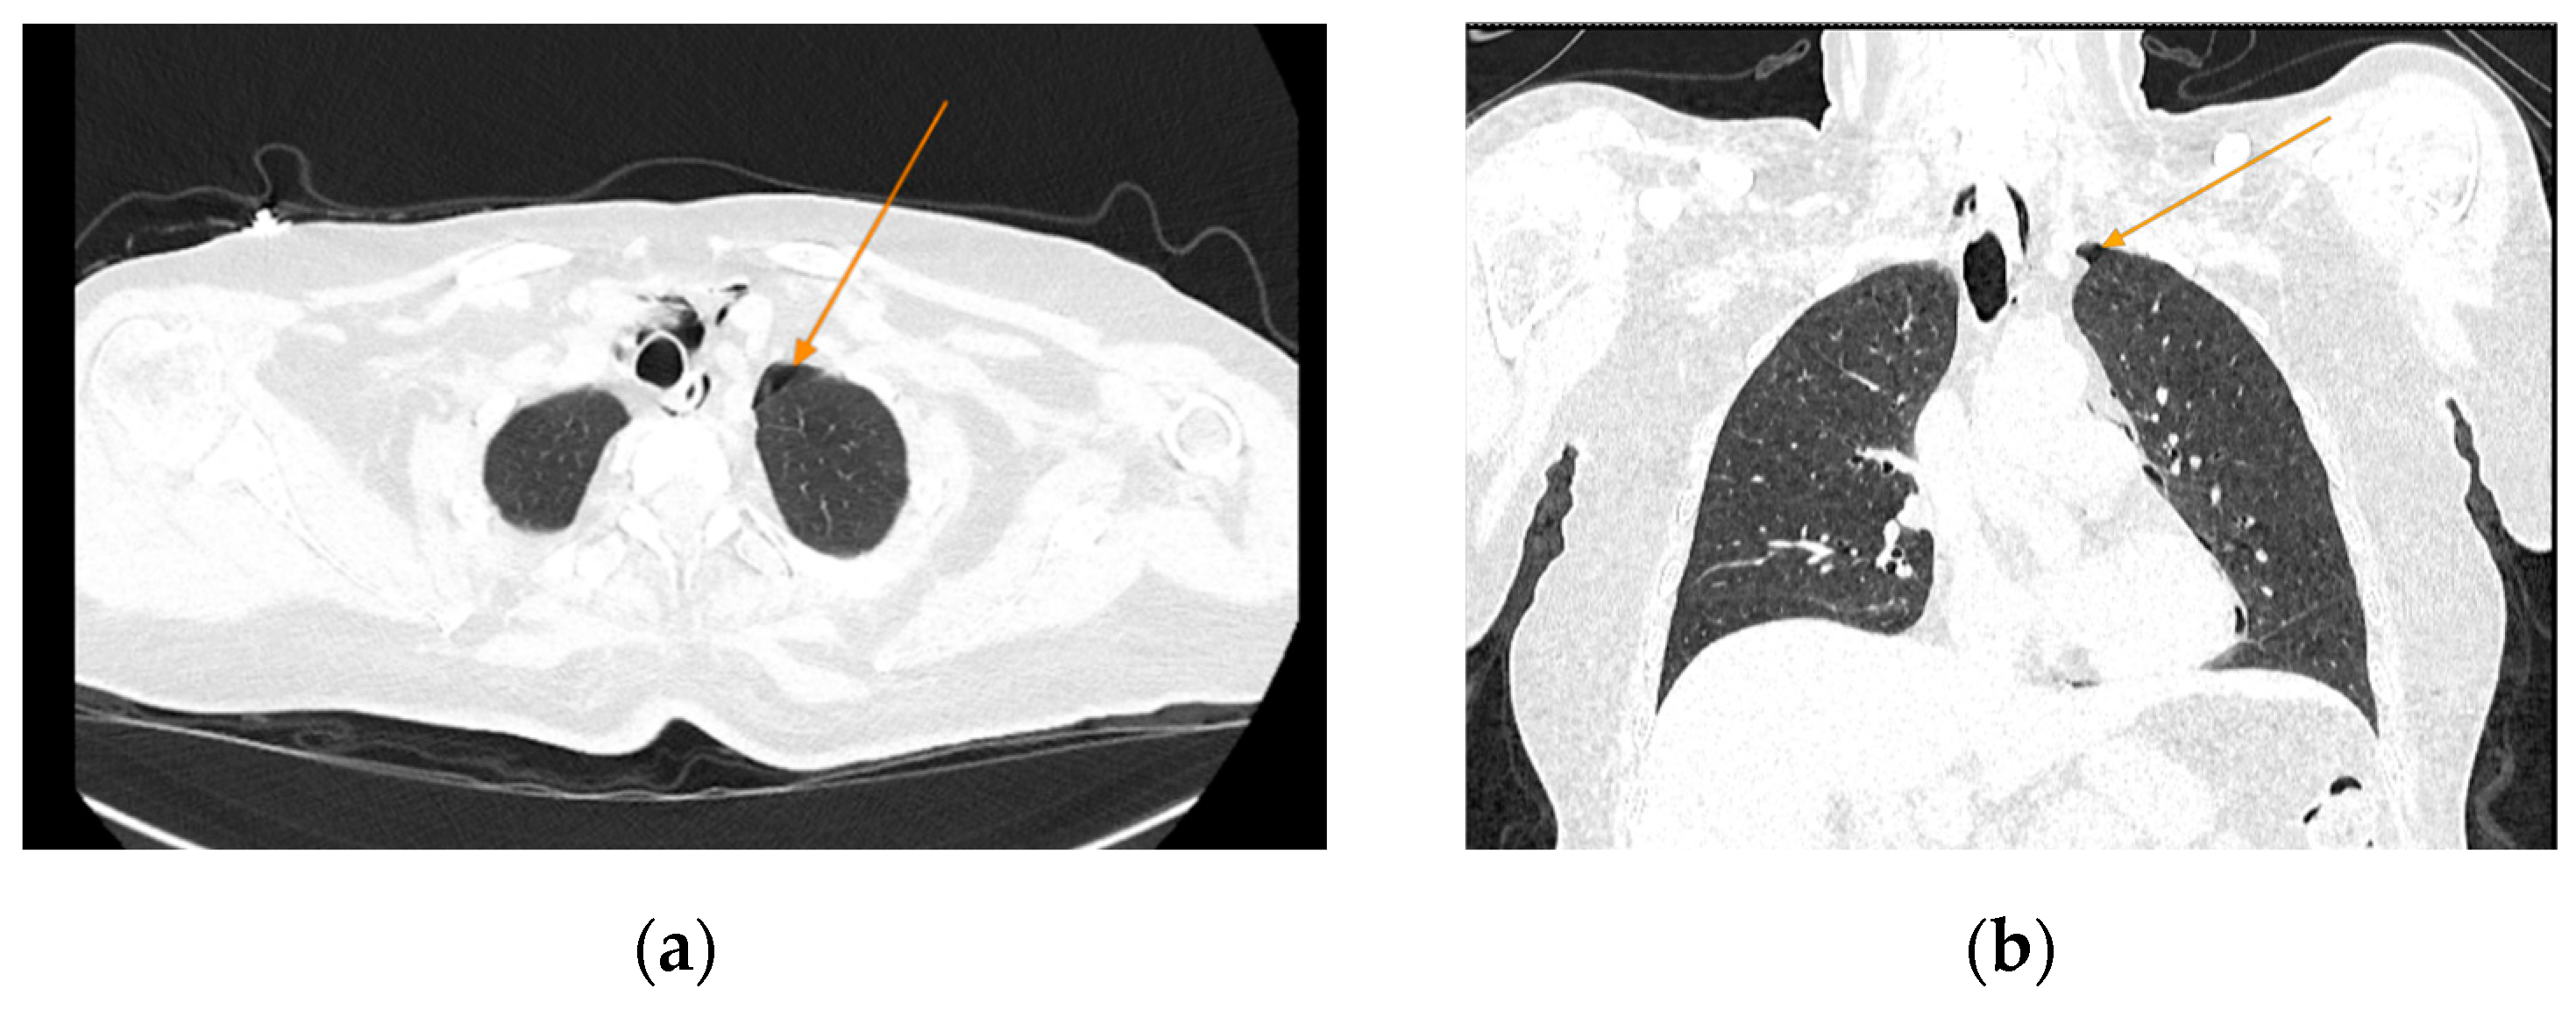

The chest CT scan performed in the emergency department (Figure 1) revealed the presence of pneumomediastinum. CT scans of the abdomen and pelvis were also performed, giving the high lipase and epigastric pain, revealing findings consistent with acute pancreatitis (with peripancreatic fluid collection, consistent with moderate acute pancreatitis per the modified CT severity index), as well as a solitary biliary stone measuring approximately 20 mm in diameter, without intra or extrahepatic biliary ducts enlargement (Figure 2).

Figure 1. Initial chest CT, arrows indicate pneumomediastinum (arrows): (a) axial view; (b) coronal view.